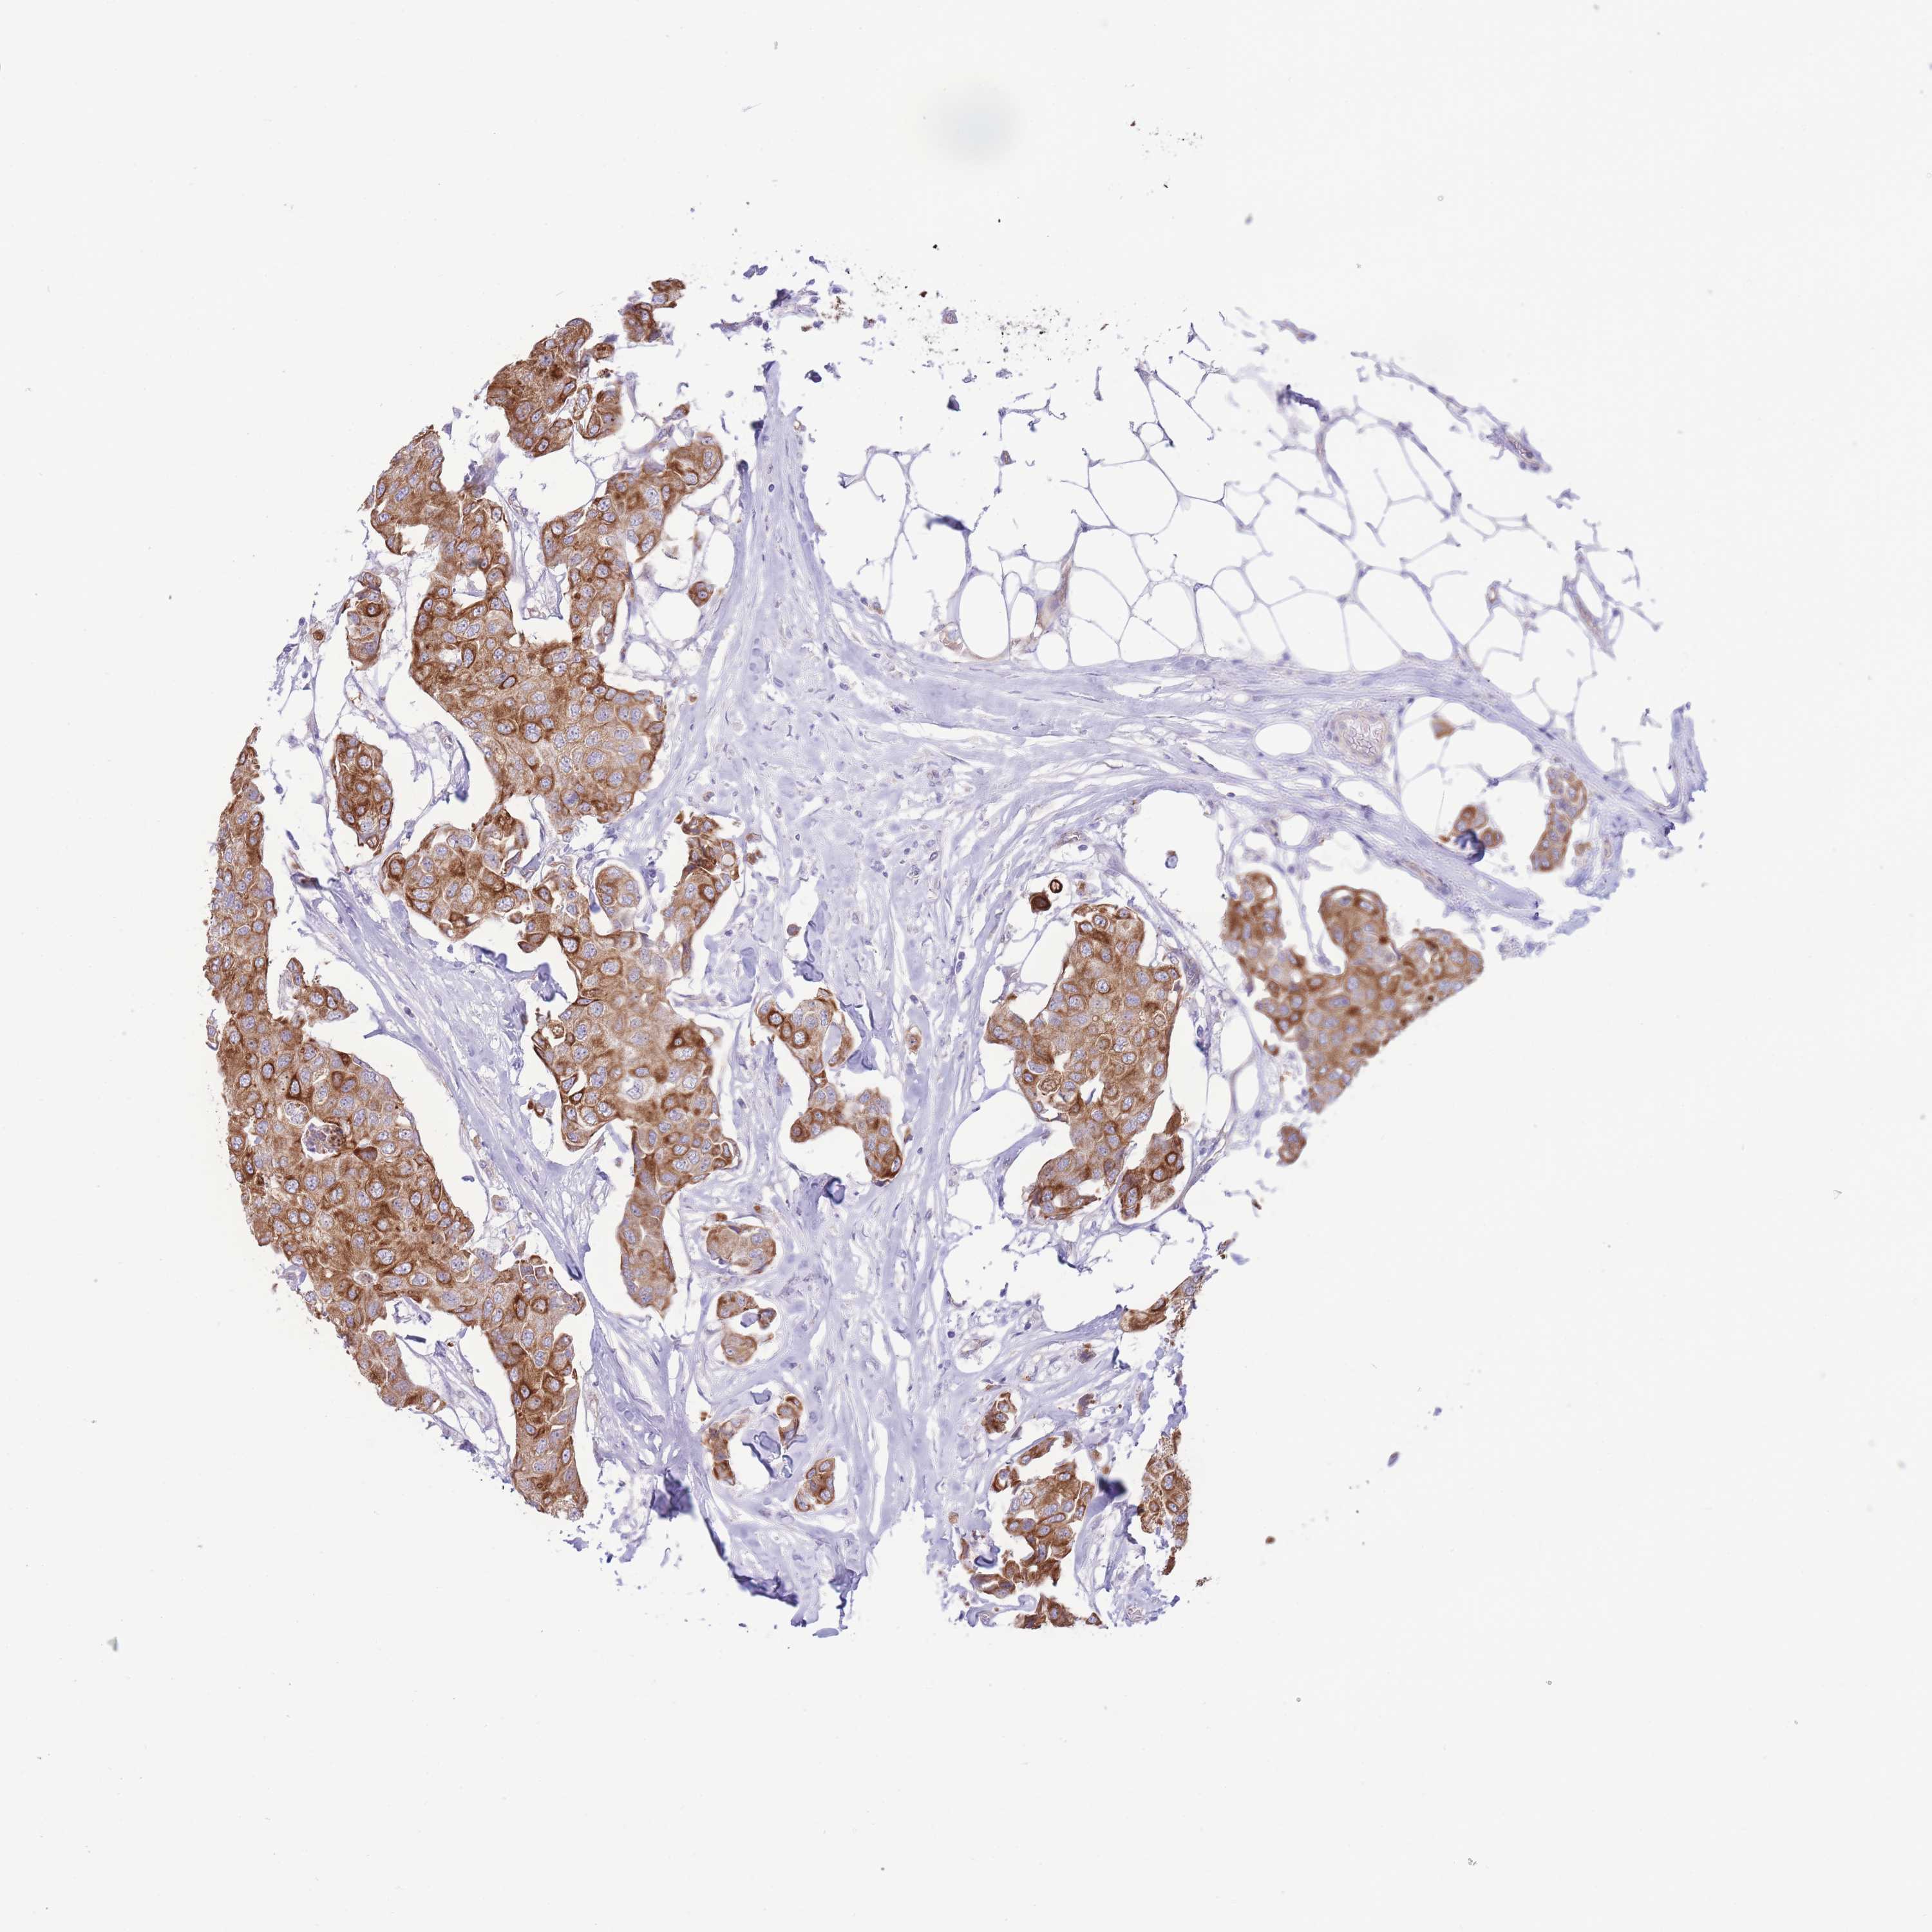

CANCER BREAST CANCER Show tissue menu

BRCA TCGA BRCA VALIDATION PROTEIN EXPRESSION